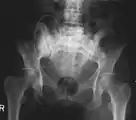

X-ray: Bone cancer in hip, spread from prostate cancer.

X-ray: Bone cancer in hip, spread from breast cancer.